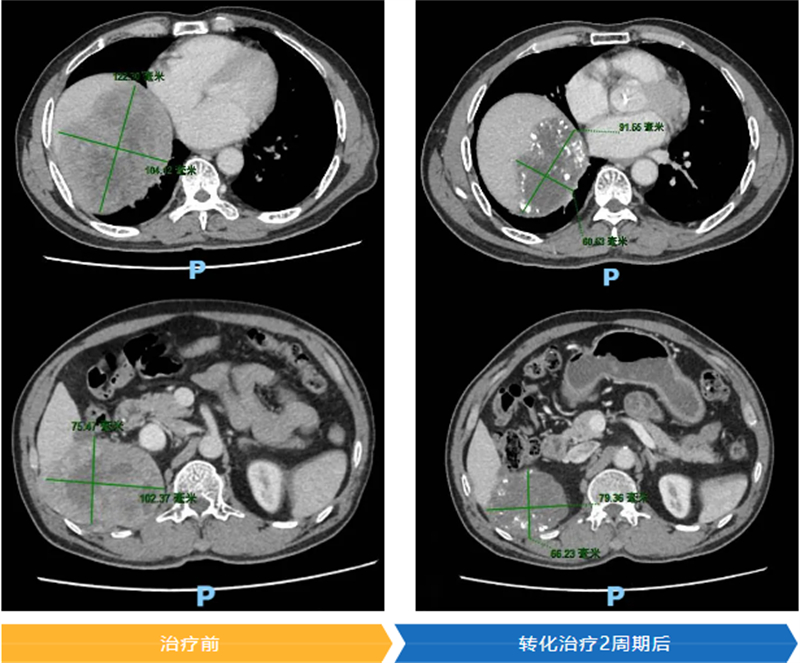

入院后,肝癌多學科聯合診療專家團隊迅速對羅大叔的病情進行聯合會診。其肝癌病灶最大直徑已達12.2cm,還侵犯了門靜脈右后支、肝右靜脈,左肝體積不足,根據原發性肝癌診療指南,已不適合直接手術。不過,專家團隊發現羅大叔左邊肝臟未受癌細胞侵襲,于是為他量身定制了“靶向+免疫+介入”三聯轉化治療方案。

經過2個周期的治療,羅大叔的腫瘤標志物降低,幾乎接近正常水平;功能性影像檢查肝腫瘤縮小,侵犯靜脈的瘤栓消退,腫瘤活性降低,左肝代償性增生,成功轉化為可手術狀態。2025年3月,醫生順利切除了羅大叔的腫瘤。術后病理回報顯示,肝癌病灶中未見存活腫瘤細胞。在快速康復外科理念的指導下,羅大叔術后1周便順利出院。出院時,醫生還特別叮囑他,要遵照醫院的肝癌全程管理方案,繼續進行后續的綜合治療,以降低腫瘤復發的風險。